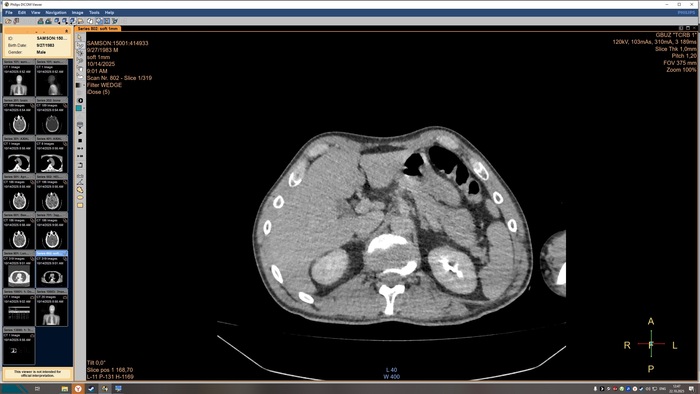

не выявлено. На прямой топограмме, серии аксиальных срезов и реконструкций получены

изображения органов грудной клетки от уровня верхней апертуры грудной клетки до уровня

задних рёберно-диафрагмальных синусов в нативном виде. Легкие в полном объёме,

пневматизация снижена. Справа в С3 выявляется бронхопневмоническая инфильтрация.

Конфигурация и просвет стволовых бронхов сохранены. Средостение обычной формы и

положения, дополнительных образований в нём не выявлено. Внутригрудные

бифуркационные и парааортальные лимфатические узлы не увеличены. Анатомия крупных

сосудов не нарушена, размеры в пределах нормы, стенки аорты и венечных артерий с очагами

кальцинатов. Плевральные утолщения и скопления жидкости отсутствуют. Диафрагма и мягкие

ткани грудной клетки без видимых патологических изменений. Признаков остеолитического, -

пластического процессов, травматических повреждений костных структур на исследованном

уровне не выявлено. ДИ по типу остеохондроза.

КТ-признаки очаговых образований головного мозга. КТ-признаки правосторонней

верхнедолевой сегментарной б/пневмонии. ДИ ГОП.

Снимки КТ